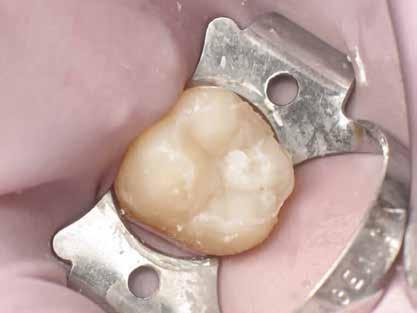

6. ábra: I. osztályú restaurációk az első moláris és a második premoláris fogakban. A széleken felesleges kompozit figyelhető meg (piros nyilak jelölik).

Az alábbi sorrend betartásával a durva finírozási fázis foganként körülbelül két-három perc alatt elvégezhető. A feles-

leges kompozit eltávolítását és a derékszögű záródási vonal kialakítását a következő klinikai képsorozat szemlélteti.